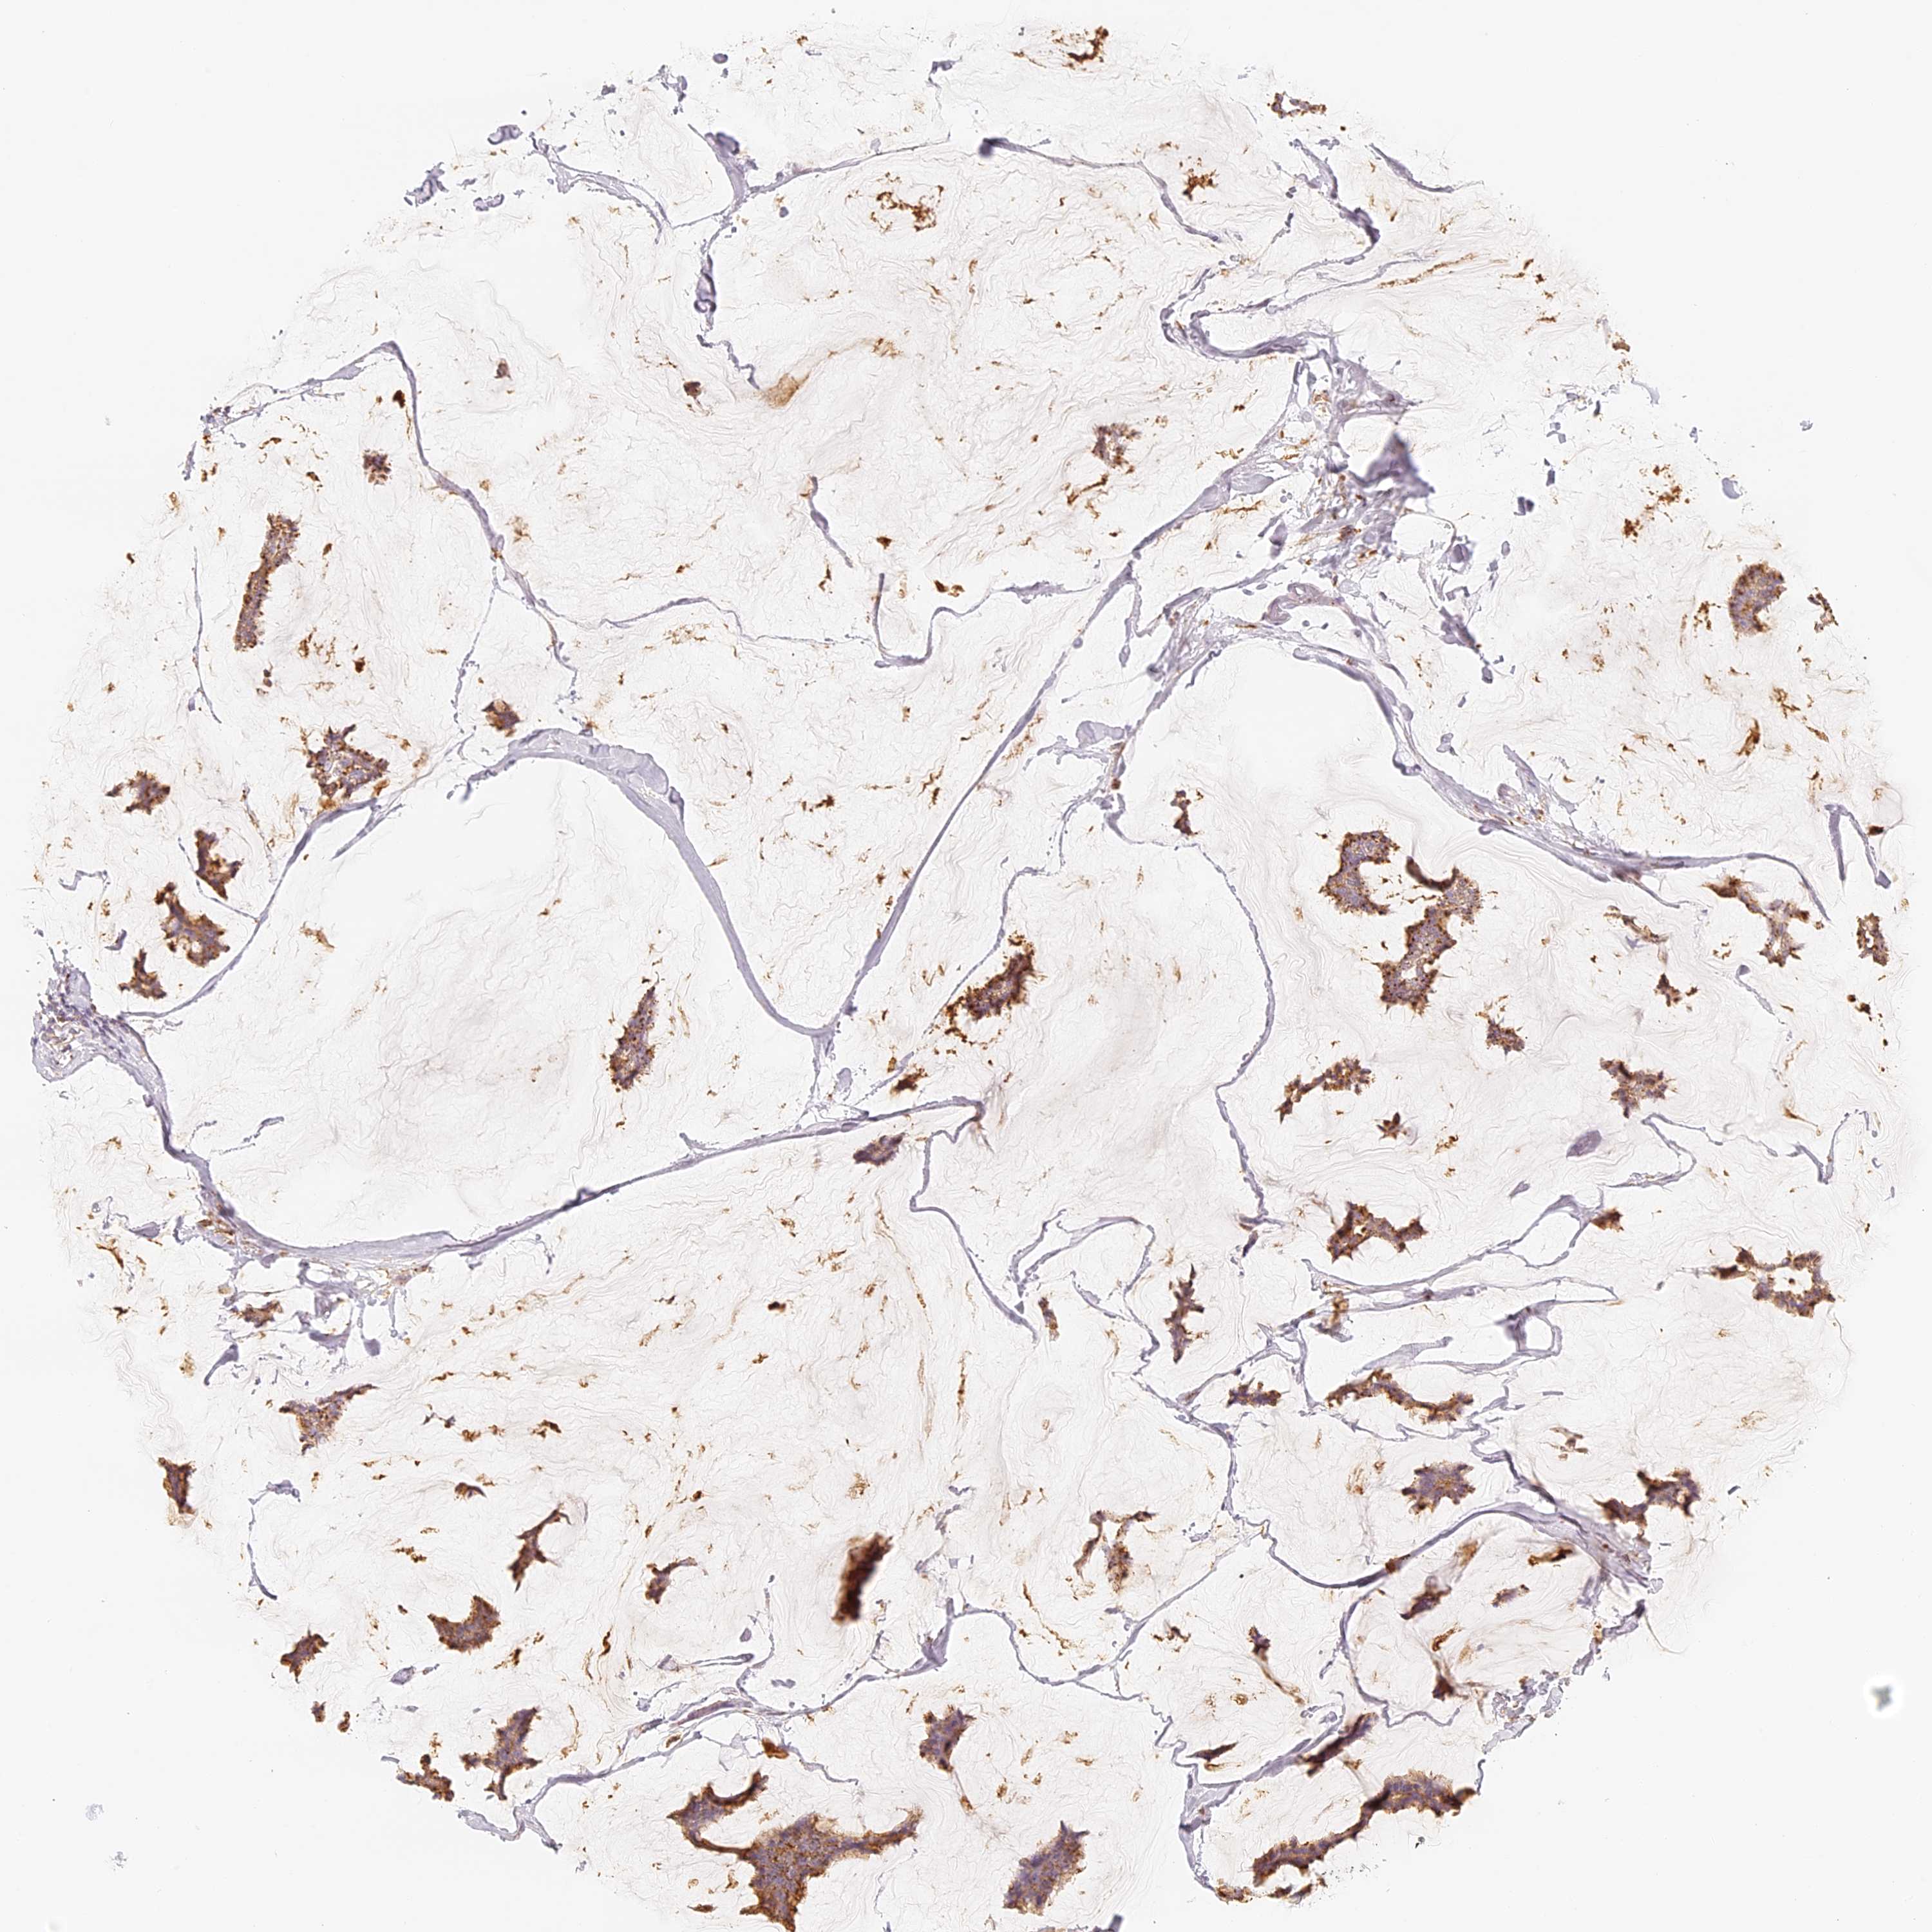

CANCER BREAST CANCER Show tissue menu

BRCA TCGA BRCA VALIDATION PROTEIN EXPRESSION